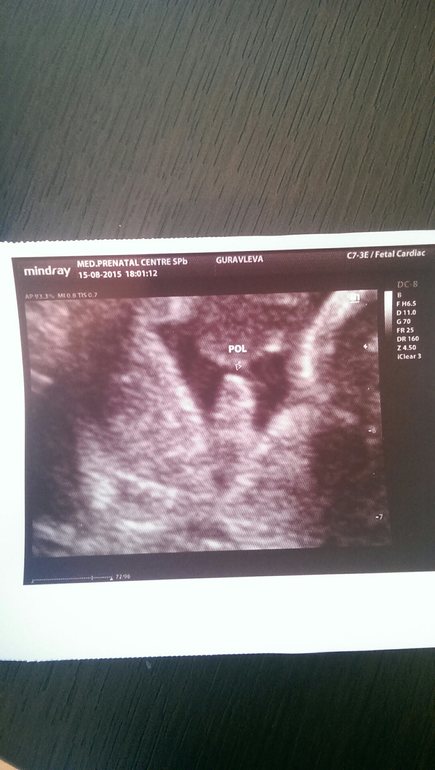

В эти выходные были на втором скрининге в 20 нед ииииии узи показало, что у нас будет братик!!! Так неожиданно, хотя нам в 12 нед предположили мальчика. По узи ттт, все хорошо, соответствует сроку. Ну и фото)))))